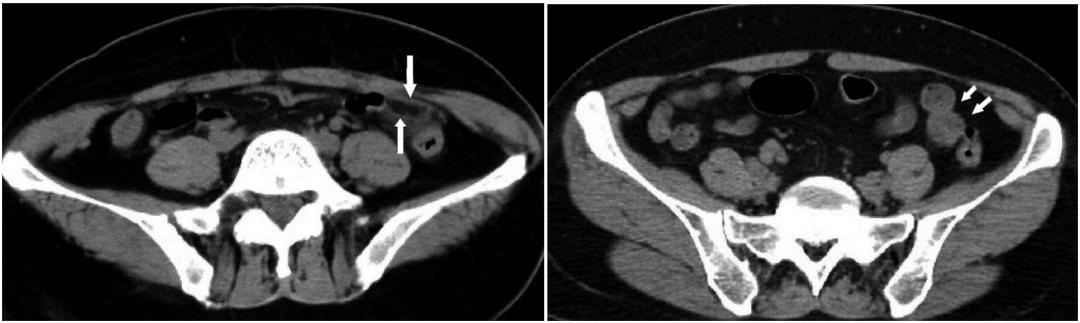

患者,女性,64岁,以“左下腹疼痛24h,进行性加重”为主诉就诊。平扫示乙状结肠前内侧见卵圆形脂肪密度病灶,周围脂肪间隙模糊,邻近肠壁无增厚。对患者给予头孢地尼胶囊,0.1g口服,3次/d,治疗7d,CT平扫示乙状结肠近端周围渗出性病变完全吸收。

降结肠肠壁的前方、侧方,贴近前腹壁,见卵圆形脂肪密度病灶,边缘呈高密度环,似“戒指”样。

患者,男性,44岁。乙状结肠肠脂垂炎。平扫轴位示乙状结肠近端旁见一直径约11mm稍高密度环影(白线所指处),环壁厚约1.9mm,中央区见点状高密度影。

患者,女性,50岁。乙状结肠肠脂垂炎。CT平扫轴位示乙状结肠旁见一直径约10mm稍高密度环影,环壁厚约2.0mm,稍高密度环影与肠壁间见狭窄的短蒂相连。